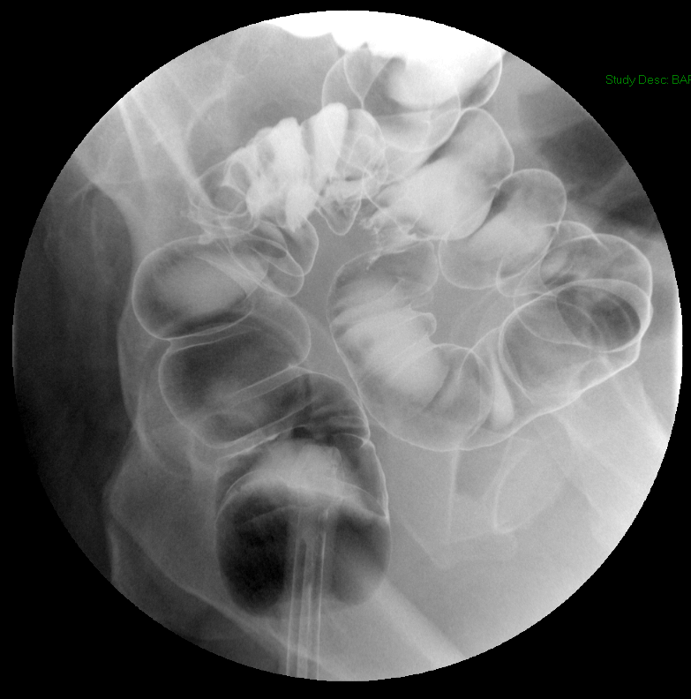

- Once the barium has reached the small bowel, you will go into the room and obtain spot images of the contrast material filled small bowel.

- Obtain images of the terminal ileum and the ileocecal valve filled with contrast material

(key image 6)

(key image 7)

(key image 8)

(key image 9)

(key image 10).

- Obtain spot images of the remainder of the small bowel

(key image 11)

(key image 12)

(key image 13)

(key image 14).

- Obtain images of all four quadrants. Use the compression paddle to separate loops of small bowel from each other.